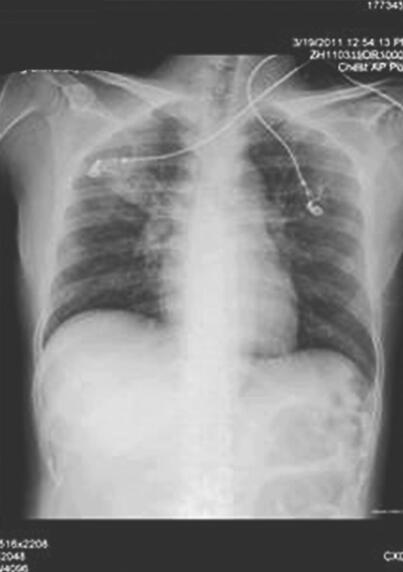

诊治经过:患者入院后3次痰找结核分枝杆菌阴性,PPD阴性,抗结核抗体阴性,ANA 1∶80,ANCA阴性,予左氧氟沙星和头孢呋辛抗感染,同时予胰岛素控制血糖,积极补液降酮体,每天入量5000ml左右(静脉输液1000ml,口服补液4000ml左右),尿量4000ml左右,1天后复查血气分析示pH 7.36,PO2 99mmHg,PCO2 26mmHg,HCO3− 14.7mmol/L,SaO2 97%,尿常规酮体阴性,胸片(图3)示双肺渗出性病变,较前吸收,5天后复查超声心动图示左心室壁运动减低,三尖瓣轻度反流,LVEF 43%。患者体温正常,血象正常,呼吸困难逐渐消失,复查胸片(图4)基本正常。9天后复查BNP 567.5pg/ml。出院后4个月随访,患者日常活动下无胸闷、气短,复查超声心动图示心内结构正常,舒张功能减退,LVEF 54%。

图3 入院后第2天复查胸片示双肺渗出性病变,较前吸收